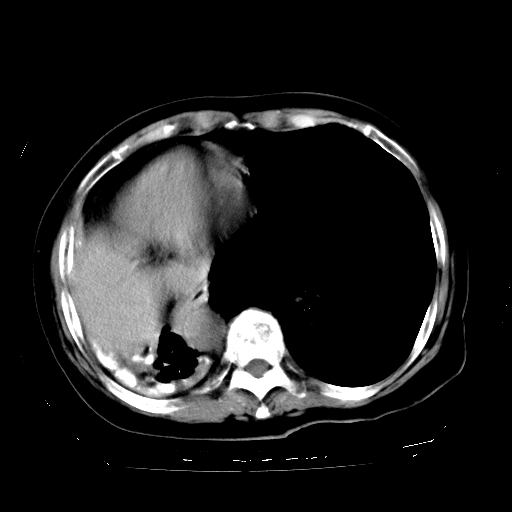

标题: CT23991:女,72岁,咳嗽、憋气一周。 [打印本页]

女,72岁,咳嗽、憋气一周,十年前曾患肺结核及胸膜结核。

右侧肺硬变,左肺代偿气肿。

1.右侧损毁肺伴胸膜钙化,2.左肺小结节灶,良性可能大,注意复查。3.肝脏左叶囊肿。4.先天性一侧肺不发育待出外(右侧胸廓无明显塌陷)。对比原片应该非常有帮助。

右侧肺毁损,左肺代偿性肺气肿,纵隔疝。